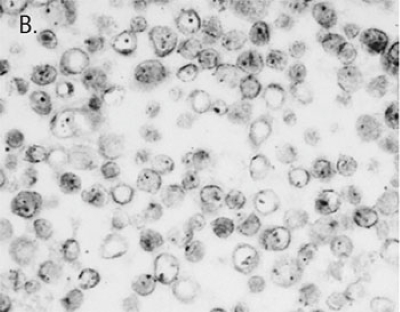

检测SiHa细胞中的HPV 16/18(1-3个HPV整合拷贝),A. 用AMPIVIEW™ HPV 16/18正义RNA探针仅检测病毒DNA,B. AMPIVIEW™ HPV 16/18反义RNA探针同时检测细胞中的病毒DNA和病毒RNA。